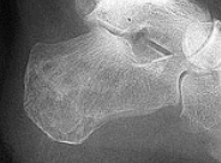

What is this? What foot type is this visible in? | Sinus tarsi/bullet hole sign. Pes cavo-varus |

What is this? What foot type is this visible in? | Double talar dome sign. Pes cavo-varus |